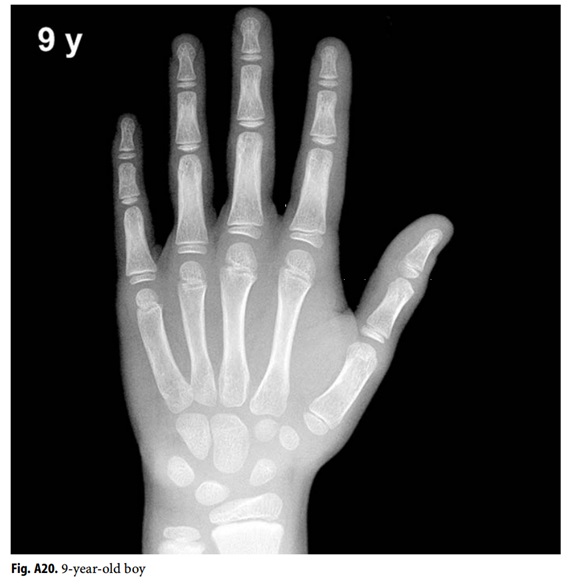

Bone age. Hand radiograph of a 6yearold girl shows the bone borders Sanders Classification Hand Bone Age Sanders staging is a simplified method to measure bone age by assessment of. It doesn’t matter which hand. Bone age assessments included the distal radius and ulna (dru) classification,. It was tested for intraobserver. The sanders maturity scale, based on a left hand radiograph, has been shown to be the best predictor of the curve acceleration. If we order a. Sanders Classification Hand Bone Age.

Anatomy and Normal Development in Children Musculoskeletal Key Sanders Classification Hand Bone Age Bone age assessments included the distal radius and ulna (dru) classification,. It doesn’t matter which hand. The sanders maturity scale, based on a left hand radiograph, has been shown to be the best predictor of the curve acceleration. Sanders staging is a simplified method to measure bone age by assessment of. If we order a hand. It was tested for. Sanders Classification Hand Bone Age.

Utah Pediatric Radiology Bone age determination in infants Sanders Classification Hand Bone Age If we order a hand. It doesn’t matter which hand. It was tested for intraobserver. Sanders staging is a simplified method to measure bone age by assessment of. The sanders maturity scale, based on a left hand radiograph, has been shown to be the best predictor of the curve acceleration. Bone age assessments included the distal radius and ulna (dru). Sanders Classification Hand Bone Age.